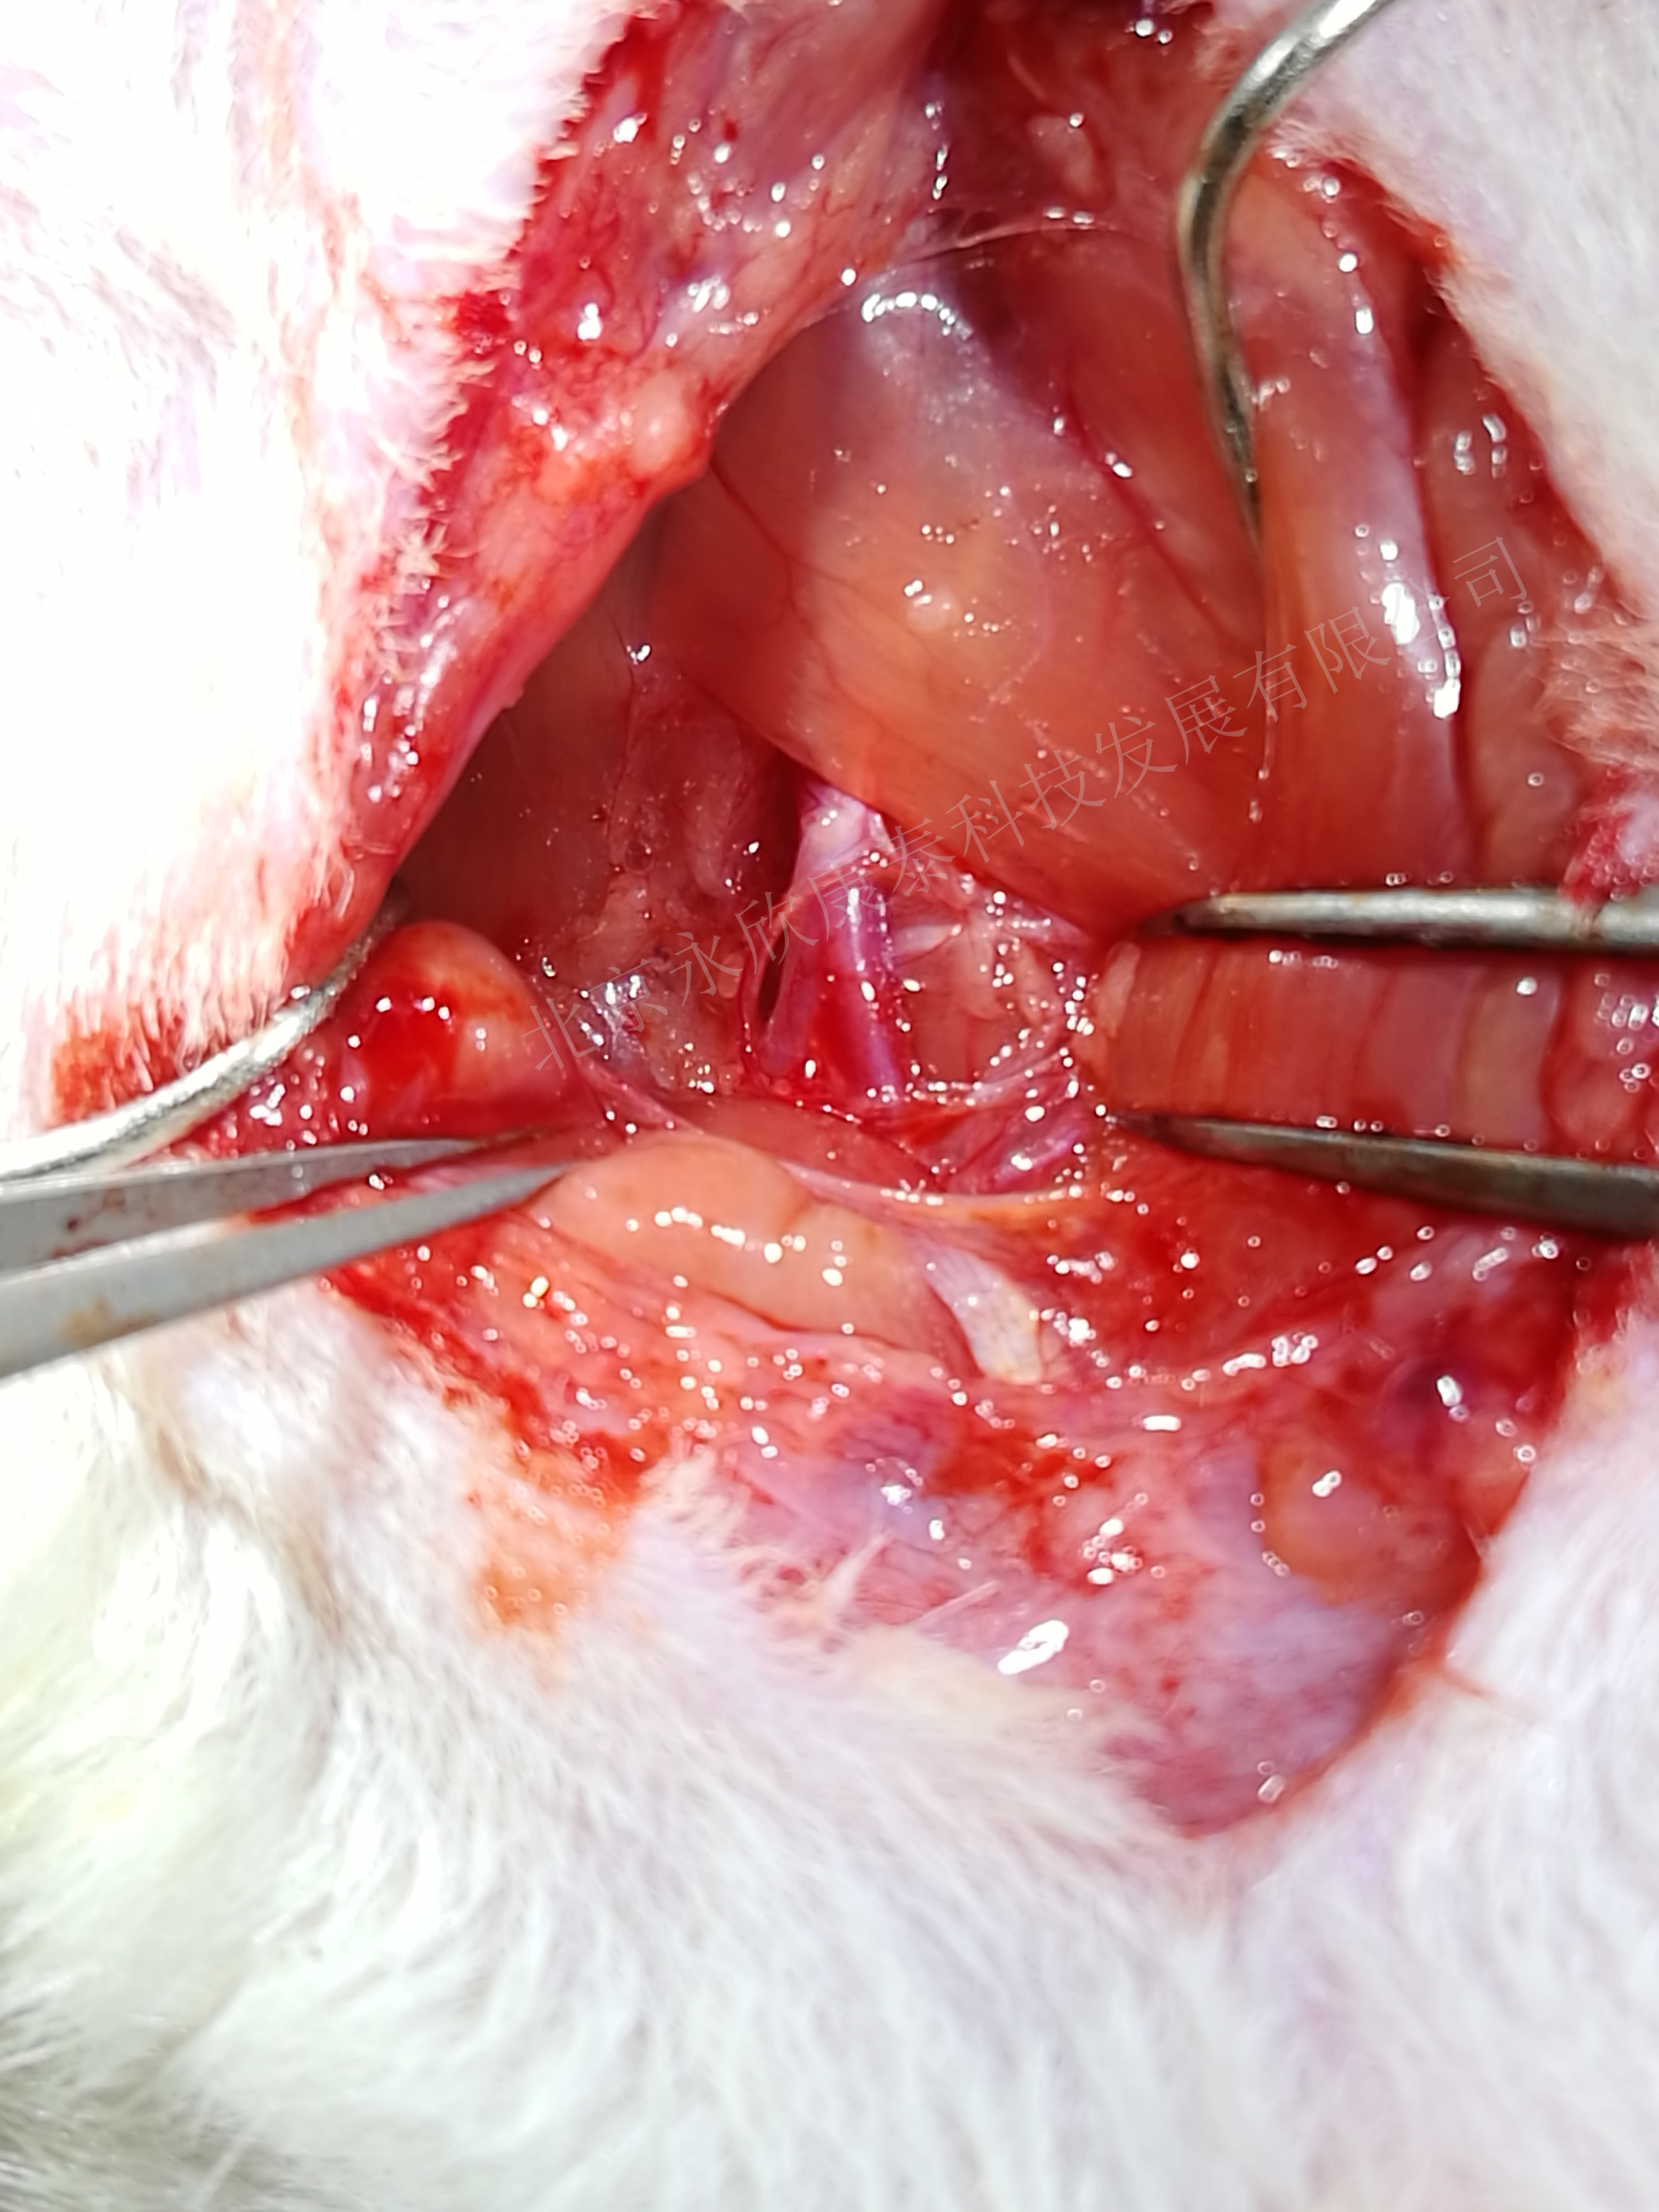

1、球囊拉伤大鼠颈动脉,致颈动脉斑块模型

2、特殊球囊、手术快速、成活率达到90%